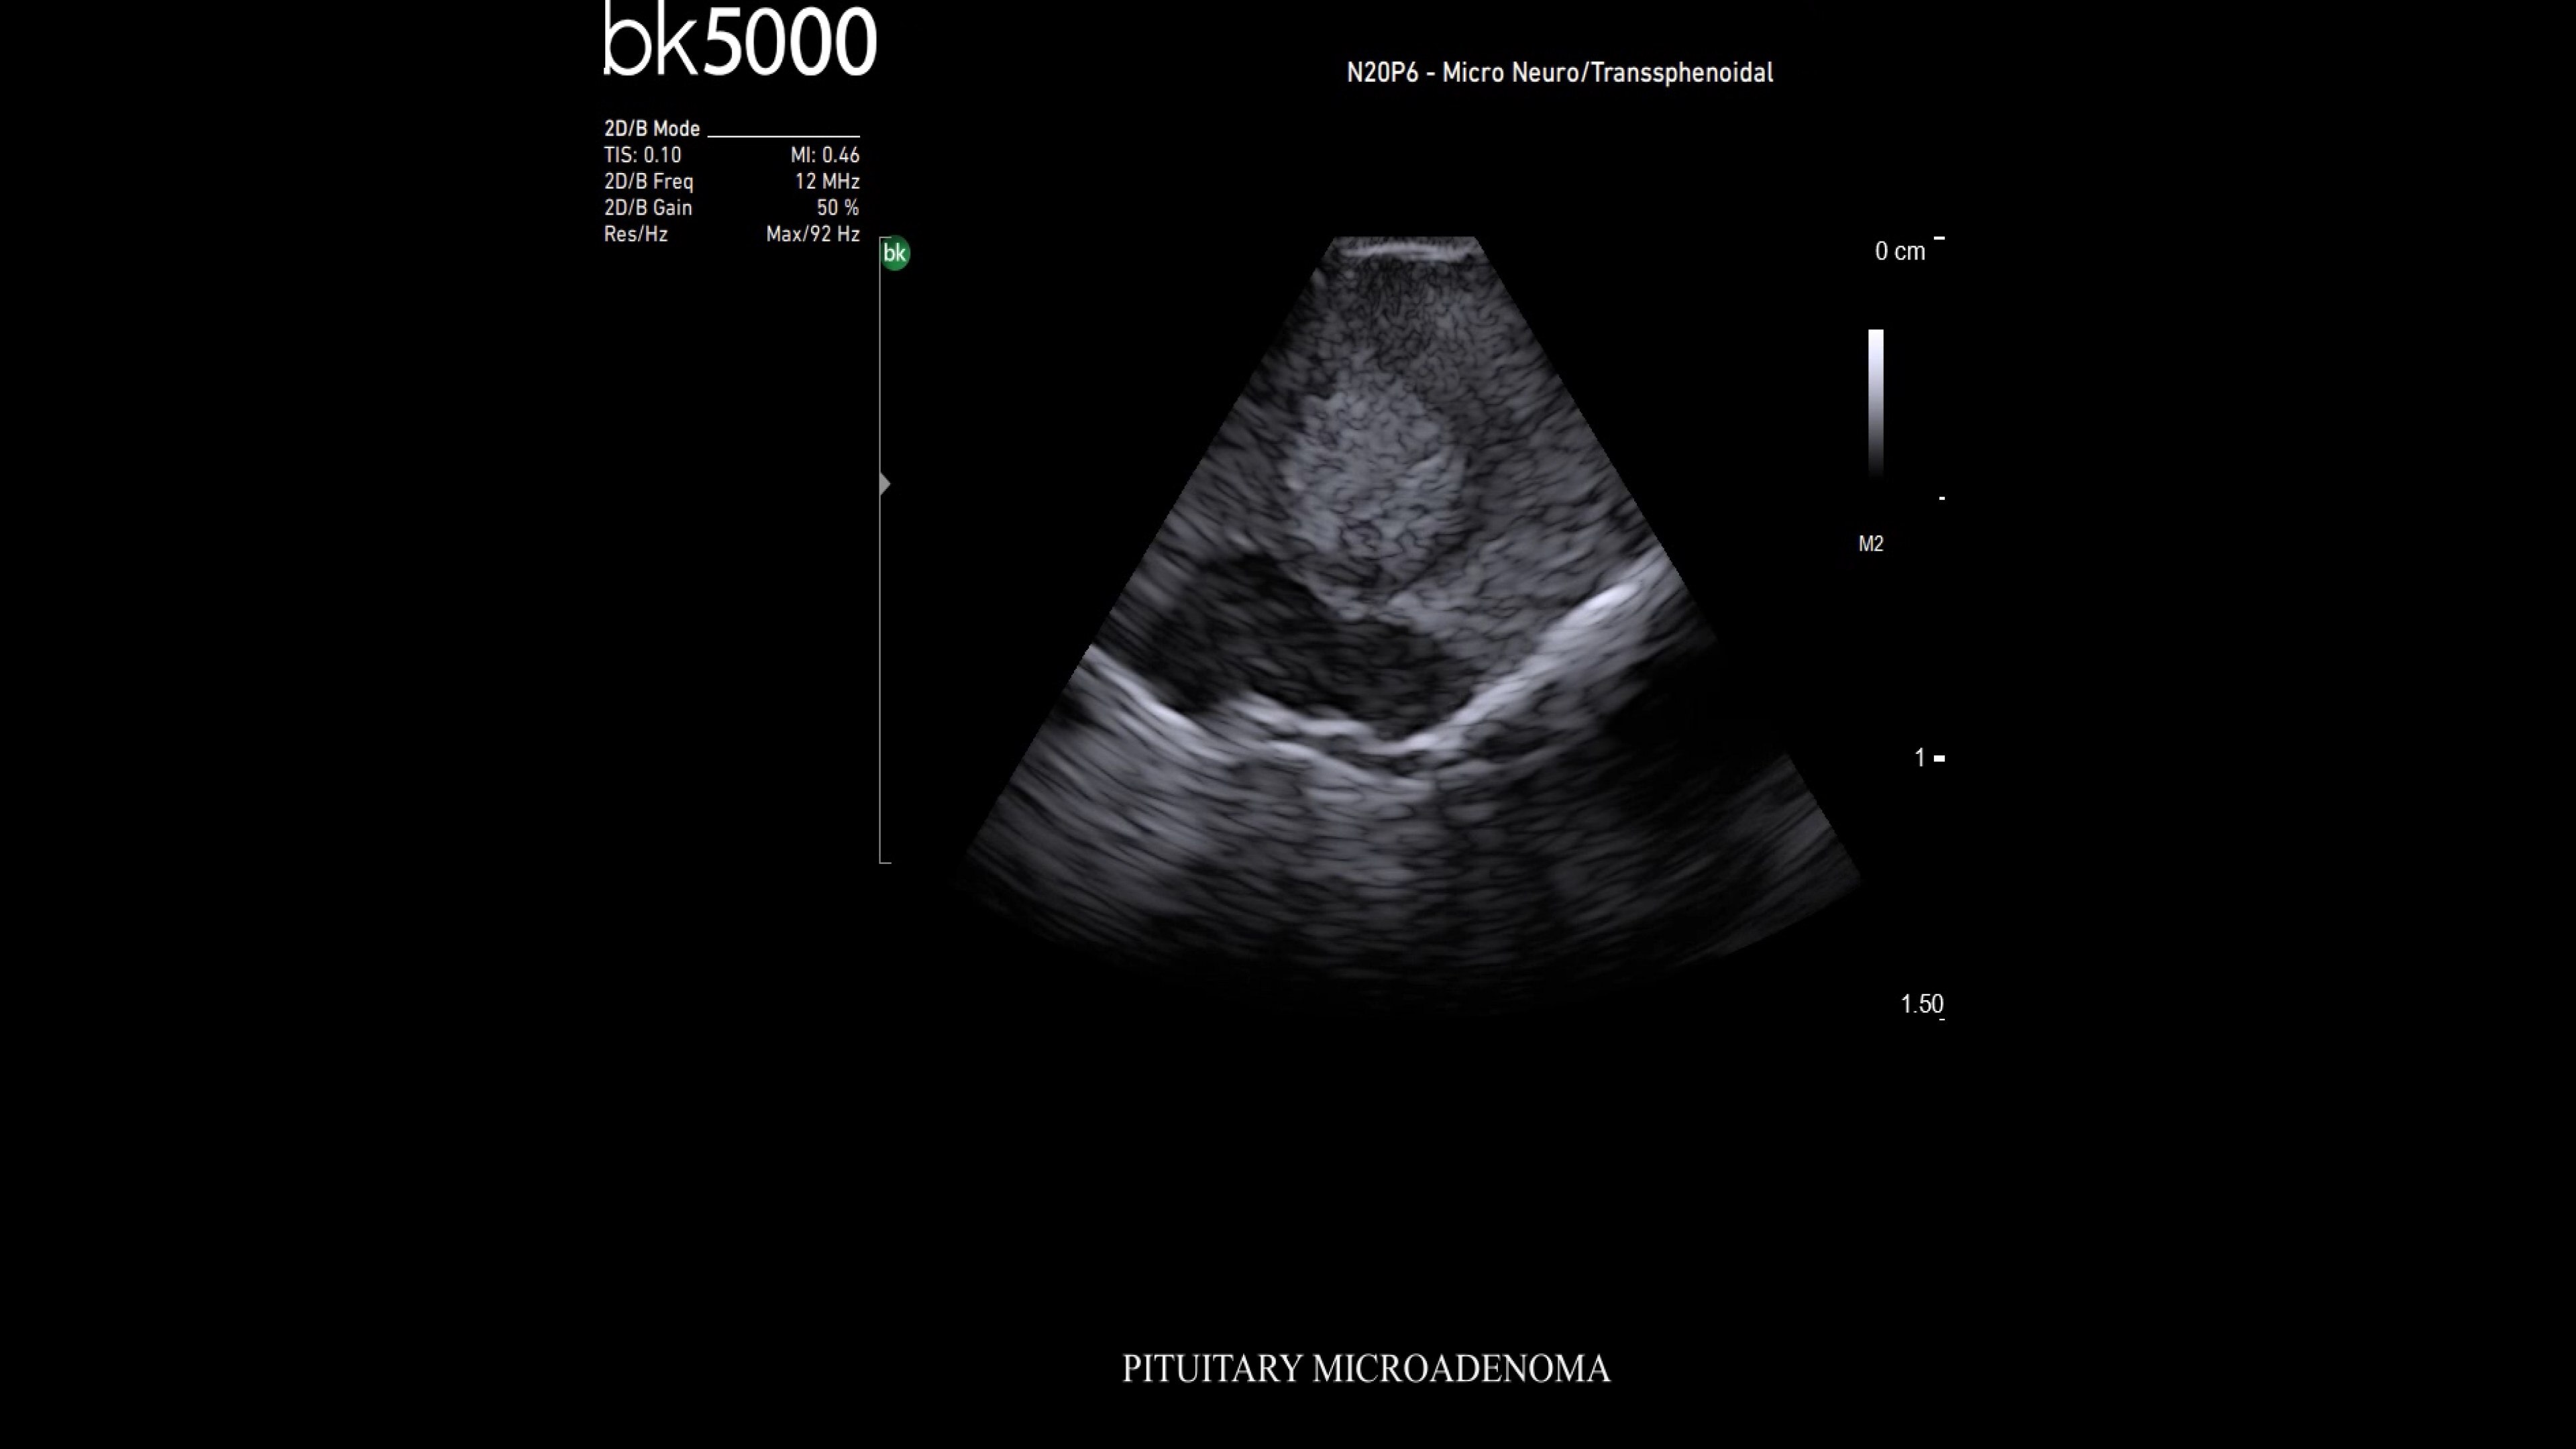

bk5000 ultrasound system

Experience the bk5000 built with remarkable image clarity and advanced features for intraoperative, robotic, and neurosurgery, enhancing surgical precision.

Precision imaging for refined surgical outcomes

The bk5000 ultrasound system offers unmatched image clarity and advanced features tailored for intraoperative, robotic, and neurosurgery applications. With intuitive controls and specialized tools, it enhances surgical precision, streamlines workflows, and ensures reliable performance in demanding environments. Experience the difference in patient care and surgical efficiency with the bk5000.

Neurosurgery

Premium ultrasound imaging in neurosurgical procedures

Ultrasound enhances neurosurgery by providing real-time navigation and lesion identification, crucial as preoperative CT/MRI data can be outdated. The bk5000 system offers high-quality images to see lesion margins and determine actions. Advanced graphics processing ensures immediate, auto-optimized images.

• Neurosurgery transducers: High-resolution, sterilizable transducers provide detailed brain and spinal cord images. The Smart™ button allows easy activation, freezing, storing, or printing of images. Disposable needle guides aid lesion targeting.

• Digital integration with Brainlab: Brainlab software offers real-time ultrasound overlay on pre-op MRI/CT, showing brain shift instantly. It scans and reconstructs 3D ultrasound data faster than intraoperative MR/CT, with no image quality loss.